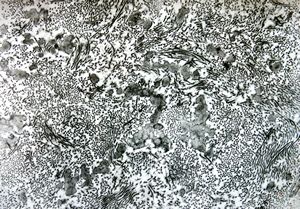

M,47y. | hypertrophic cardiomyopathy - left ventricle ( N - nucleus, T- transversally oriented, L- longitudinally oriented myofibrils )

M,47y. | hypertrophic cardiomyopathy - left ventricle-crossing of myofilaments can also be caused arteficially with bioptom